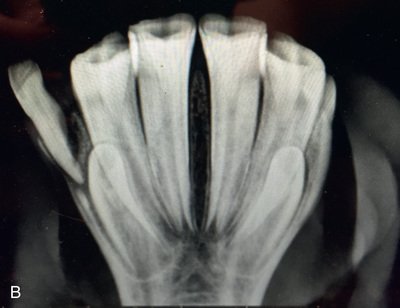

| Teeth | Occlusal (Fig. 24.56) | In the mouth as far caudal as the patient will allow. | Maxillary: dorsal to head Mandibular: ventral to head. | Maxillary: direct beam downward Mandibular: direct beam upward at 60-80 degrees from vertical, depending on the conformation of incisors. | Difficult as patient not likely to cooperate without chemical restraint. Need lower exposure than for cheek teeth. |